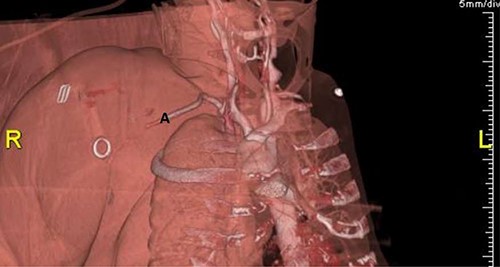

Plain radiographs of the right humerus and shoulder did not show any fracture or dislocation. A computed tomography (CT) scan with arterial phase angiography did not show and acute fracture of the cervical spine, but did reveal an abrupt cessation in flow in the right axillary artery secondary to traumatic occlusion of the vessel at the junction of segment 2 going into segment 3 with significant surrounding haematoma (Figs. 1 and 2).

3D reconstruction of CT angiography showing abrupt cessation of flow beyond segment 1 of the right axillary artery (A).